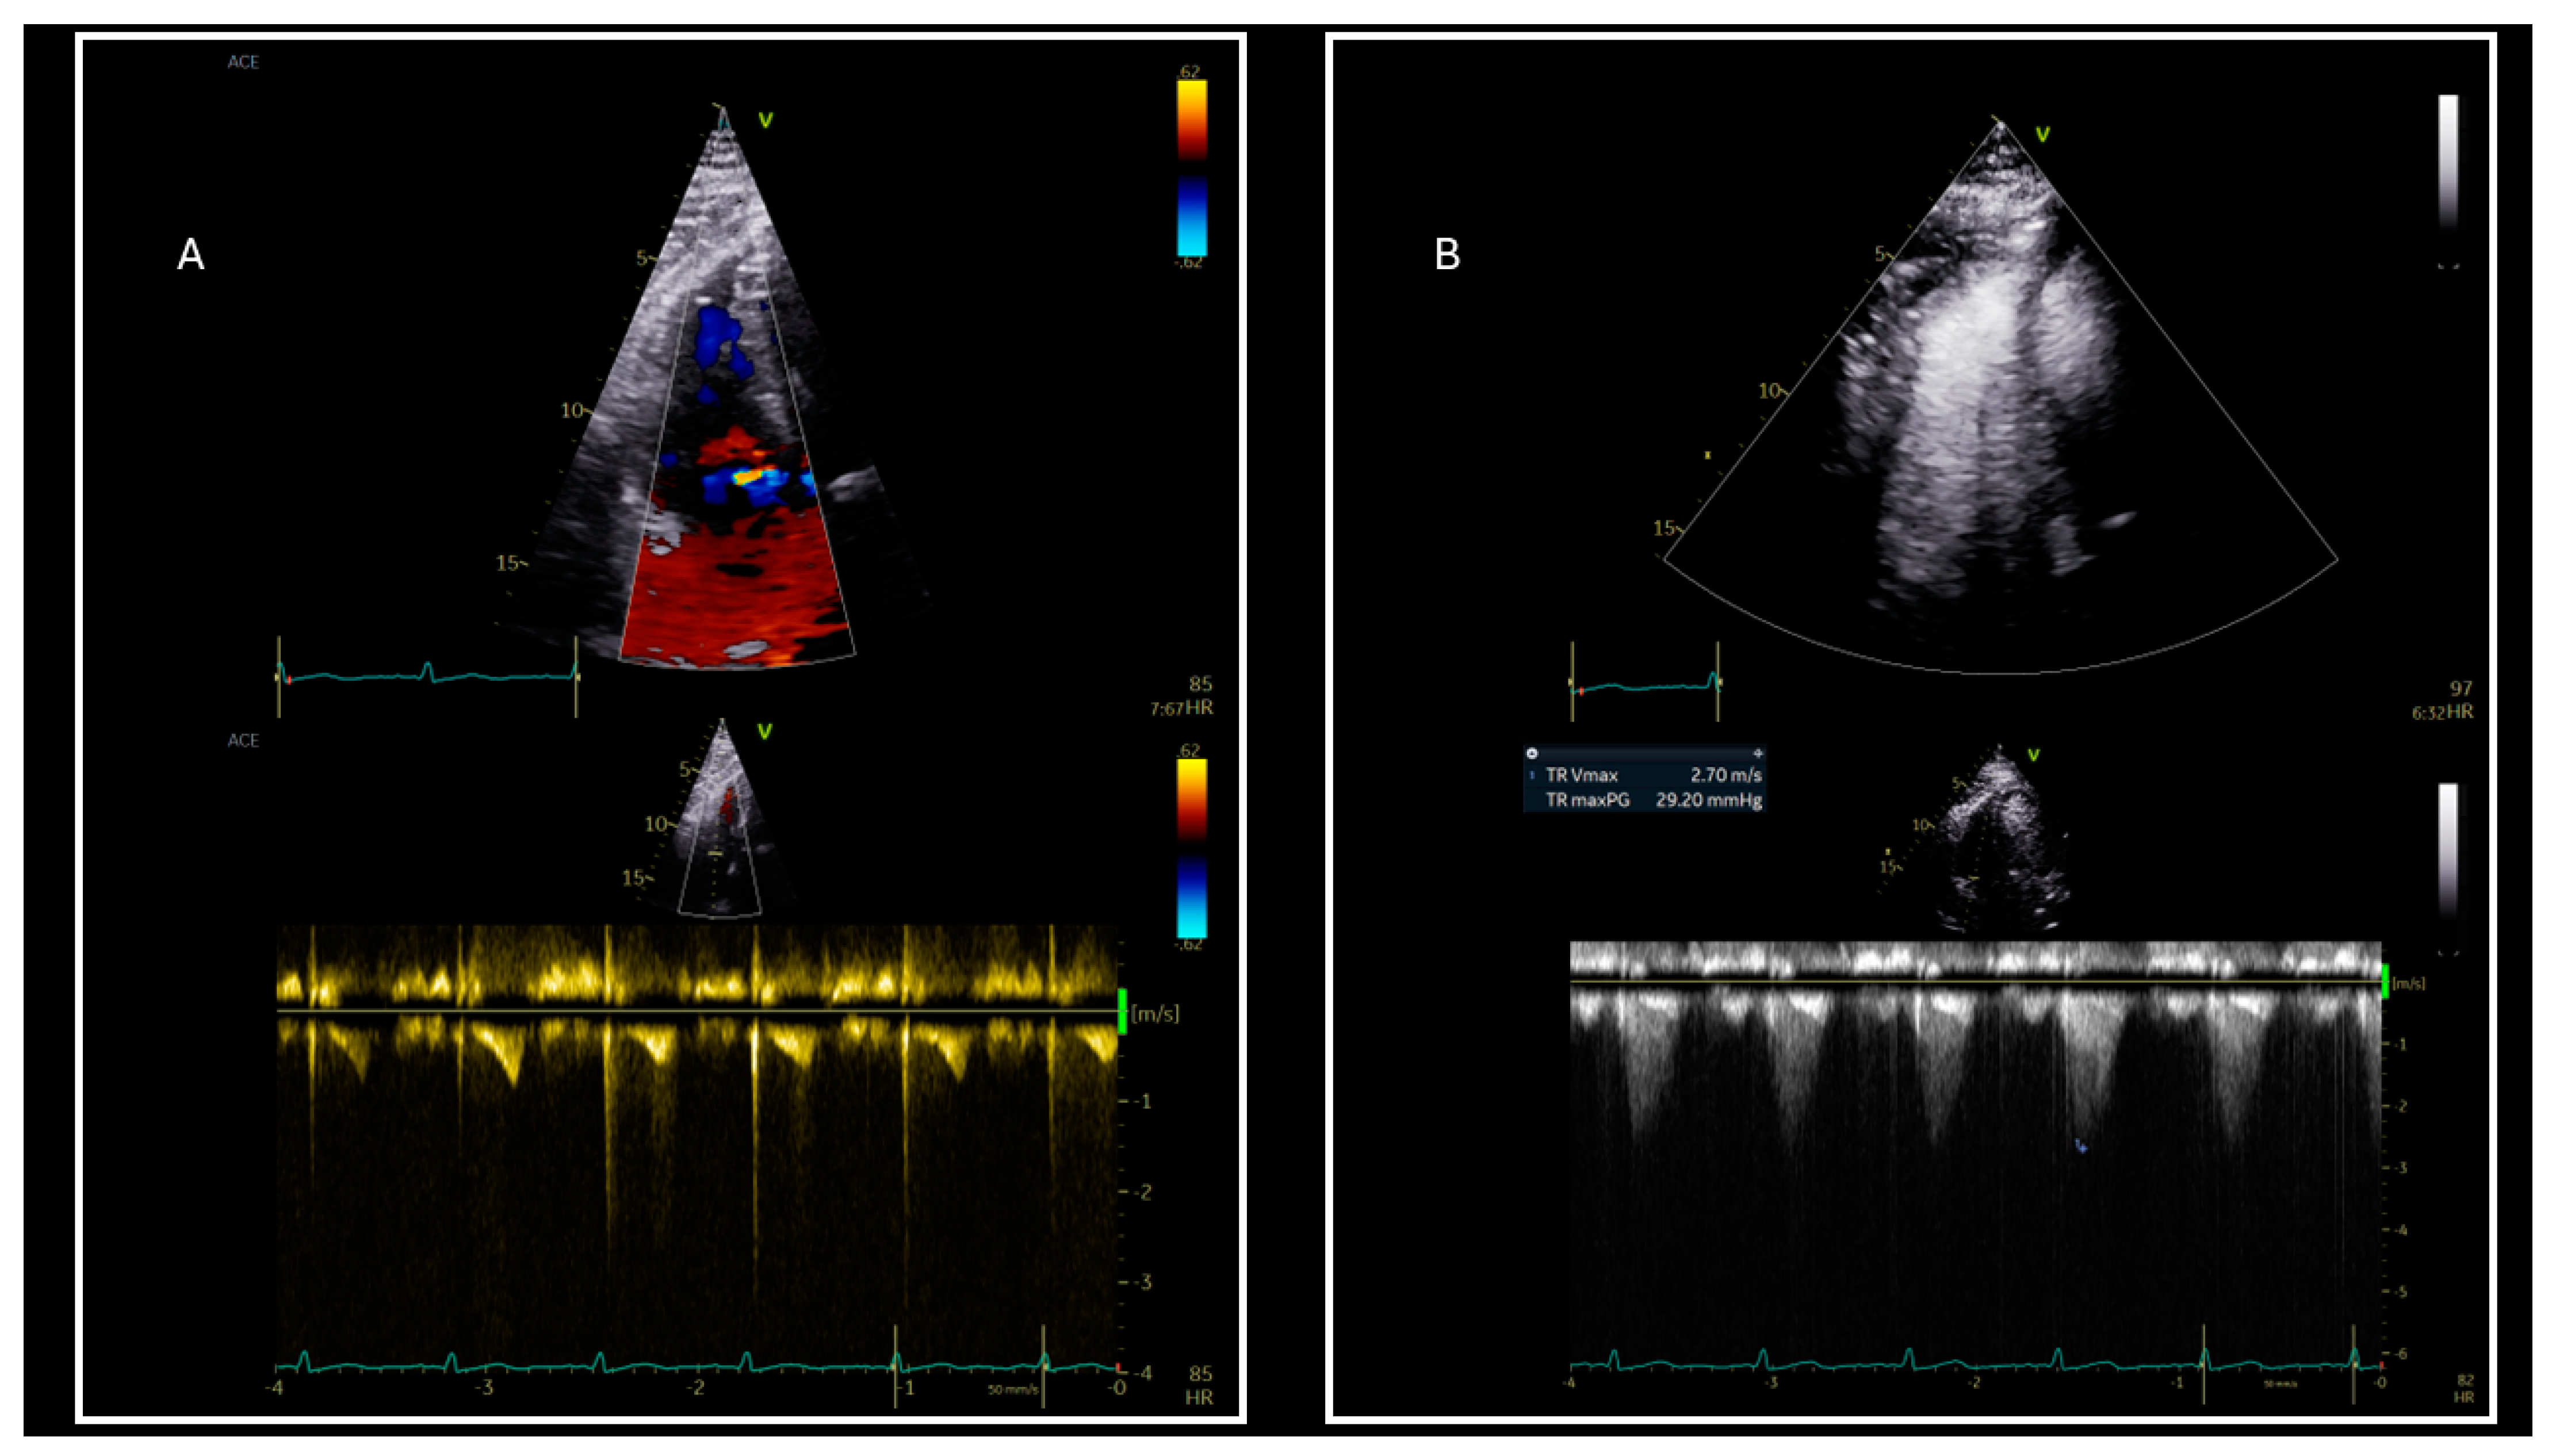

| Use of contrast agents for accurate tricuspid regurgitation maximum velocity estimation |

| Tricuspid regurgitation Vmax | |

| TR Vmax > 2.8 m/sec or systolic pulmonary artery pressure > 35 mmHg | ||||